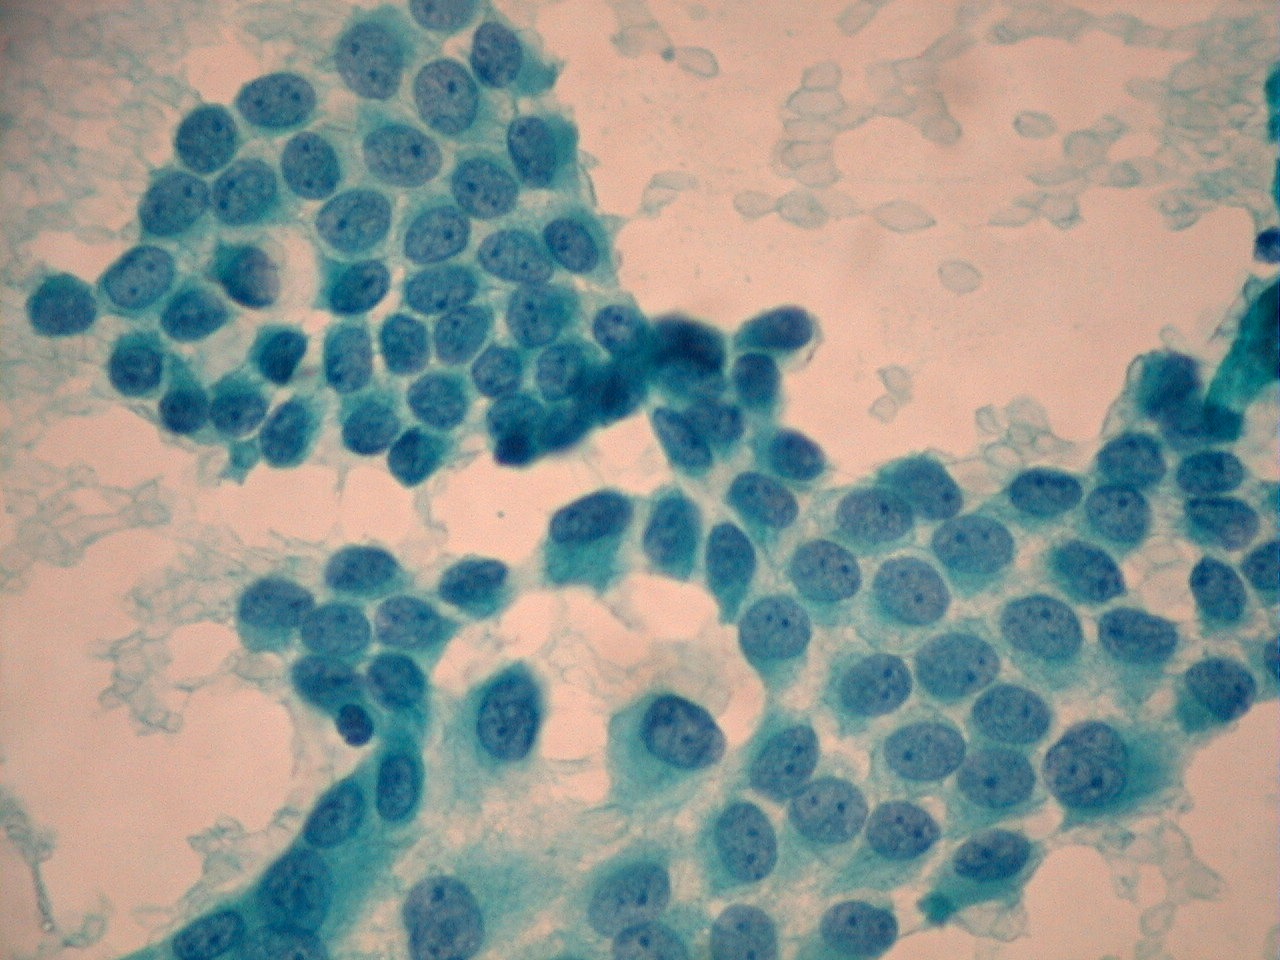

V Congreso Virtual Hispanoamericano de Anatomía Patológica CARCINOMA

Source: www.uninet.edu